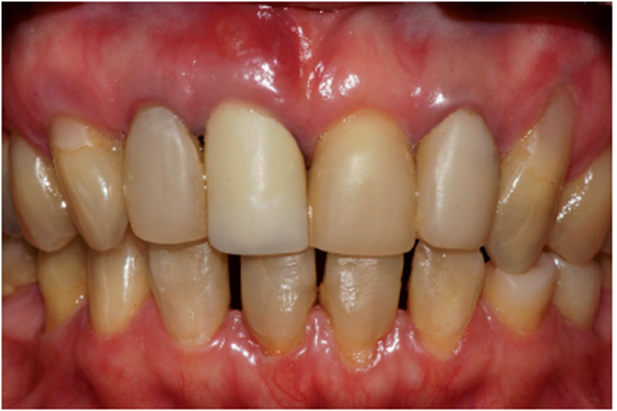

Paciente A.N., sexo feminino, 54 anos, procurou a clínica odontológica com fistula na região do elemento 11 (Figura 1). Foi solicitada tomografia computadorizada Cone Beam da região (Figura 2). Ao exame tomográfico foi diagnosticada a lesão periapical extensa, com perda óssea, envolvendo o elemento 11 (Figura 3). O plano de tratamento proposto foi a exodontia do elemento 11, curetagem da lesão e instalação imediata de um implante Cone Morse, juntamente com o procedimento de ROG, fazendo uso de biomaterial de origem bovina (Bio-Oss 0,25) e membrana de PTFE-d (Cytoplast TXT–200, Osteogenics – Lubbock TX, EUA) no mesmo momento cirúrgico.